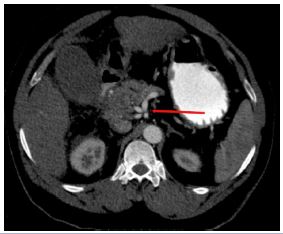

363 out of 388 cases showed a normal trifurcation pattern of the coeliac trunk (Uflacker I) representing 93.5 % of the total cases. Among the commonest anomalies among the coeliac, trunk variations were Type V Uflacker in the form of the gastro-splenic trunk with CHA arising from the aorta (most common anomaly) (Figure 1) representing 20 % of cases followed by Uflacker types II, III, IV & VIII (Figure 2) each type found in 4% of cases.

Figure 2: Volume-rendered image showing the separate origin of CHA (Yellow arrow), LGA (Blue arrow) & Splenic artery (Green arrow) from the aorta.